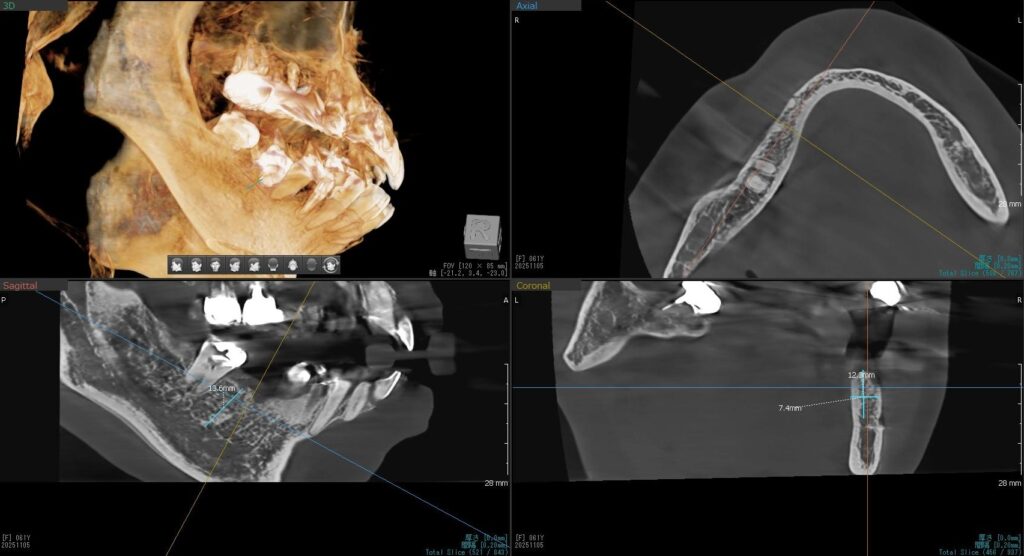

今回の患者様はインプラント植立を希望され、右下7番目の植立が決まりました。

ドリルの先端を細い物から徐々に大きい物に変えながら、植立するインプラント体のネジの部分を除いた胴の部分の太さに合わせた大きさの穴を開けていきます。

開けた穴に、専用道具を使ってネジを締めるように長さ2センチ程のインプラントを骨に埋め込んでいきます。

しっかりとインプラント埋め込まれた後は、動揺がないか、噛んだ時に当たらないかなどを確認して、最後にパノラマ写真を撮影して今回のオペは終了となりました。